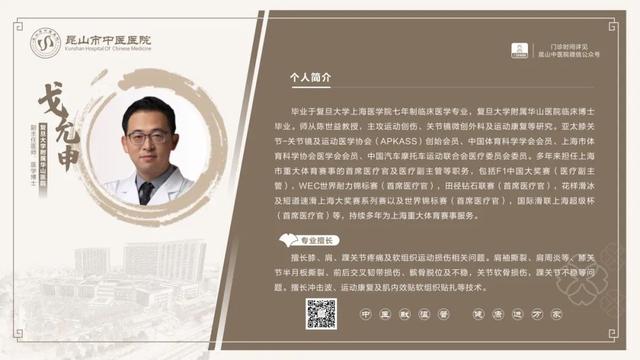

6��23��-6��29�������dz���ר�ҽ���